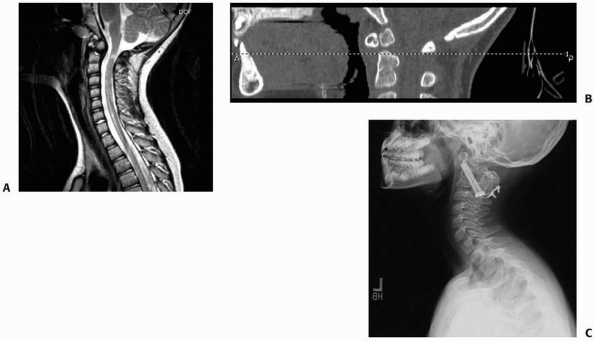

The advantages of an early MRI are the ability to allow mobilization if

no injury is present and the early detection of an unrecognized spinal

fracture to allow proper treatment. MRI also is useful in evaluating

patients with SCIWORA. MR angiography (MRA) has replaced standard

arteriography for evaluation of the vertebral arteries in patients with

upper cervical spine injuries who have suspected arterial injuries.168

MRI also remains the best imaging modality for evaluating injuries of

the intervertebral disks and is especially useful to detect disk

herniation in adolescent

patients with facet joint injuries that may require operative reduction.

![]() |

|

FIGURE 18-12 MRI depicts injury to the cervical cord and upper cervical spine.